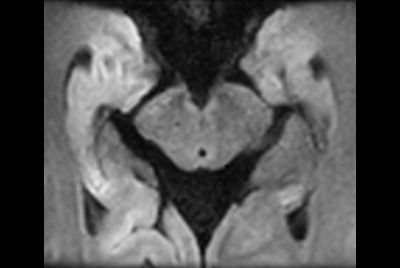

Pediatric pelvis with fistula